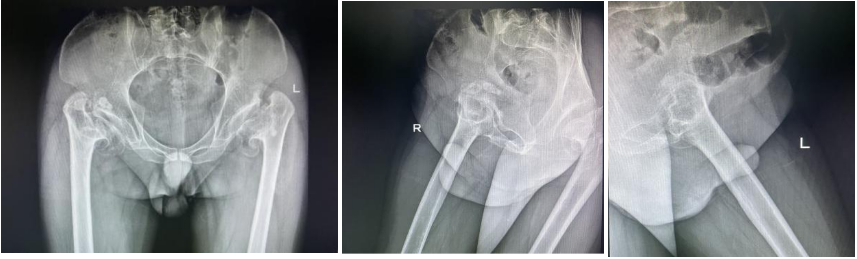

12月,针对不等长的“罪魁祸首”——右侧髋关节,郝阳泉教授团队亮出“精准医疗”利器,以三大核心技术突破实现手术精度与疗效的双重飞跃:

术前三维精准规划:依托CT三维重建与3D打印技术,1:1复刻病变关节模型,在模型上完成手术“沙盘推演”,精准测算肢体延长所需的长度与角度参数,为术中操作绘制毫米级“路线图”,从源头规避手术误差。

微创入路保障视野:采用DAA直接前方入路,经肌肉间隙微创进入病灶,既减少了手术创伤与出血量,更凭借前方清晰视野,实现术中双下肢长度的实时精准比对与关节稳定性测试,为等长重建提供关键保障。

术式创新突破瓶颈:面对髋臼发育不良、股骨头上移的复杂情况,团队借助3D导航技术,一方面将髋臼杯精准植入正常解剖位置,重建髋关节旋转中心;另一方面创新采用“阶梯化肌肉松解”技术,在完整保护软组织的前提下,无需股骨截骨即可将股骨远端轻柔下拉至预定位置,完美矫正肢体短缩。

整套手术流程环环相扣、精准可控,将右侧肢体与左侧已置换关节的长度误差控制在临床可忽略的毫米级范围内,实现了从“代偿平衡”到“解剖平衡”的本质跨越,展现了团队在3D打印个体化规划与微创技术融合应用上的深厚造诣。